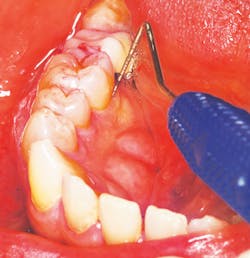

The goal of true periodontal regenerative therapy for periodontal disease is the restoration of the lost form and function of the peridontium with new cementum, a functionally oriented periodontal ligament, and most importantly, formation of new alveolar bone.

Traditional periodontal treatment utilizing only SRP with or without antimicrobial therapy often results in only repair of the periodontium. Periodontal repair implies healing with connective tissue and/or long junctional epithelium that does not fully restore architecture and form (i.e., scar tissue). Regeneration is the body’s reproduction of lost tissue and/or bone to its original form and that should be the goal of treatment.

To achieve predictable periodontal therapy results, a guided bone/tissue regeneration procedure (GTR/GBR) is indicated that includes the use of bone-grafting products (e.g., enamel matrix derivative) to regenerate the lost tissue and, most importantly, the bone.5-8